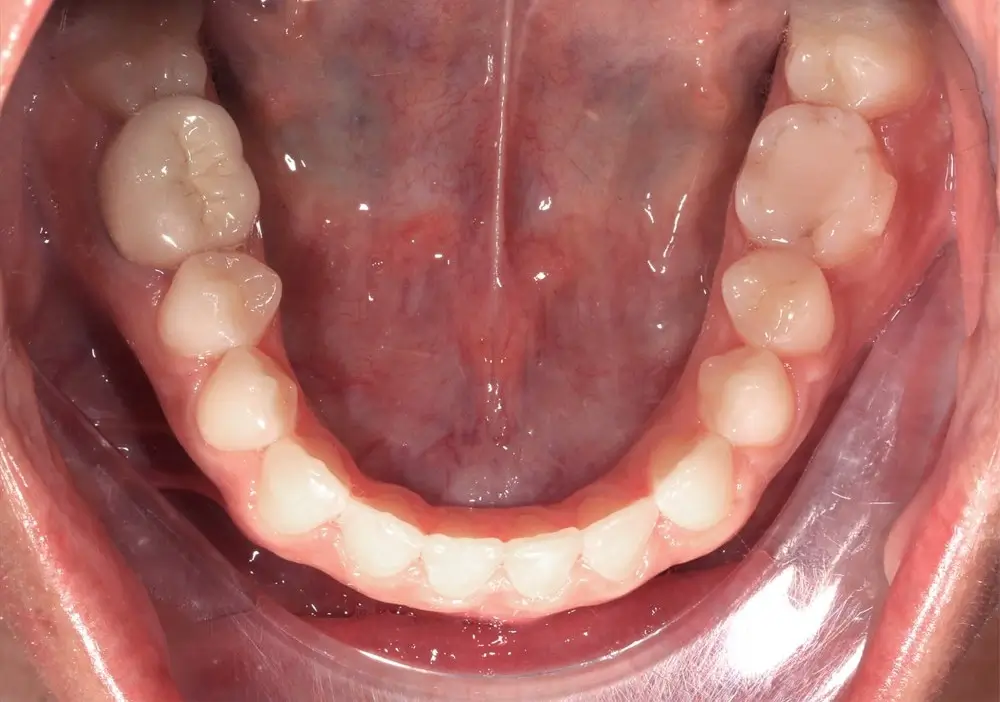

Открытый прикус - Кейс 4

Эффективность устранения дефекта прикуса посредством элайнеров FlexiLigner.

Результаты лечения